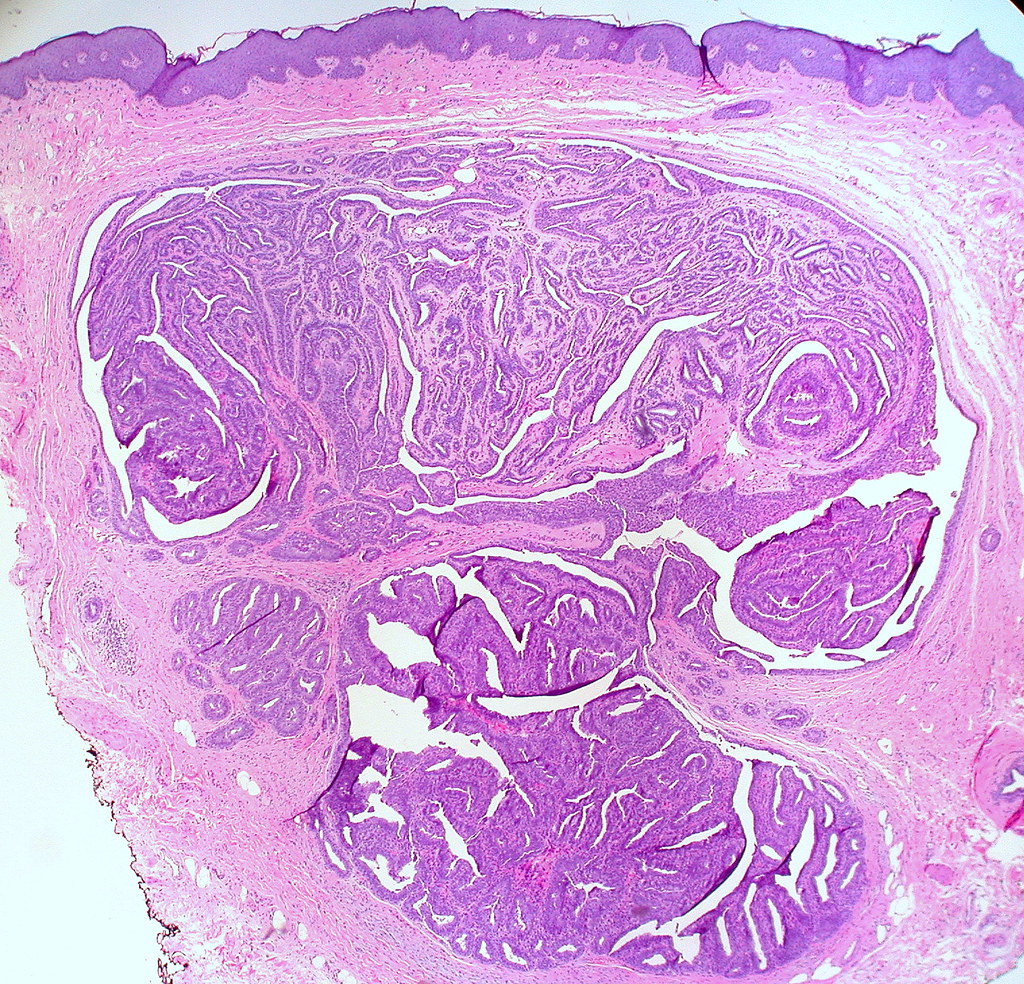

From www.flickr.com

Hidradenoma Papilliferum of the Vulva Punch biopsy from a … Flickr Punch Biopsy Vulva When the area is numb, the provider will remove a tiny piece (sample) of the changed skin. This article covers the process of taking a vulval punch biopsy. Punch biopsy is useful if the lesion is small enough for complete excision by the biopsy tip. This is done with a small sharp tool. After a vulvar biopsy, healing usually generally. Punch Biopsy Vulva.